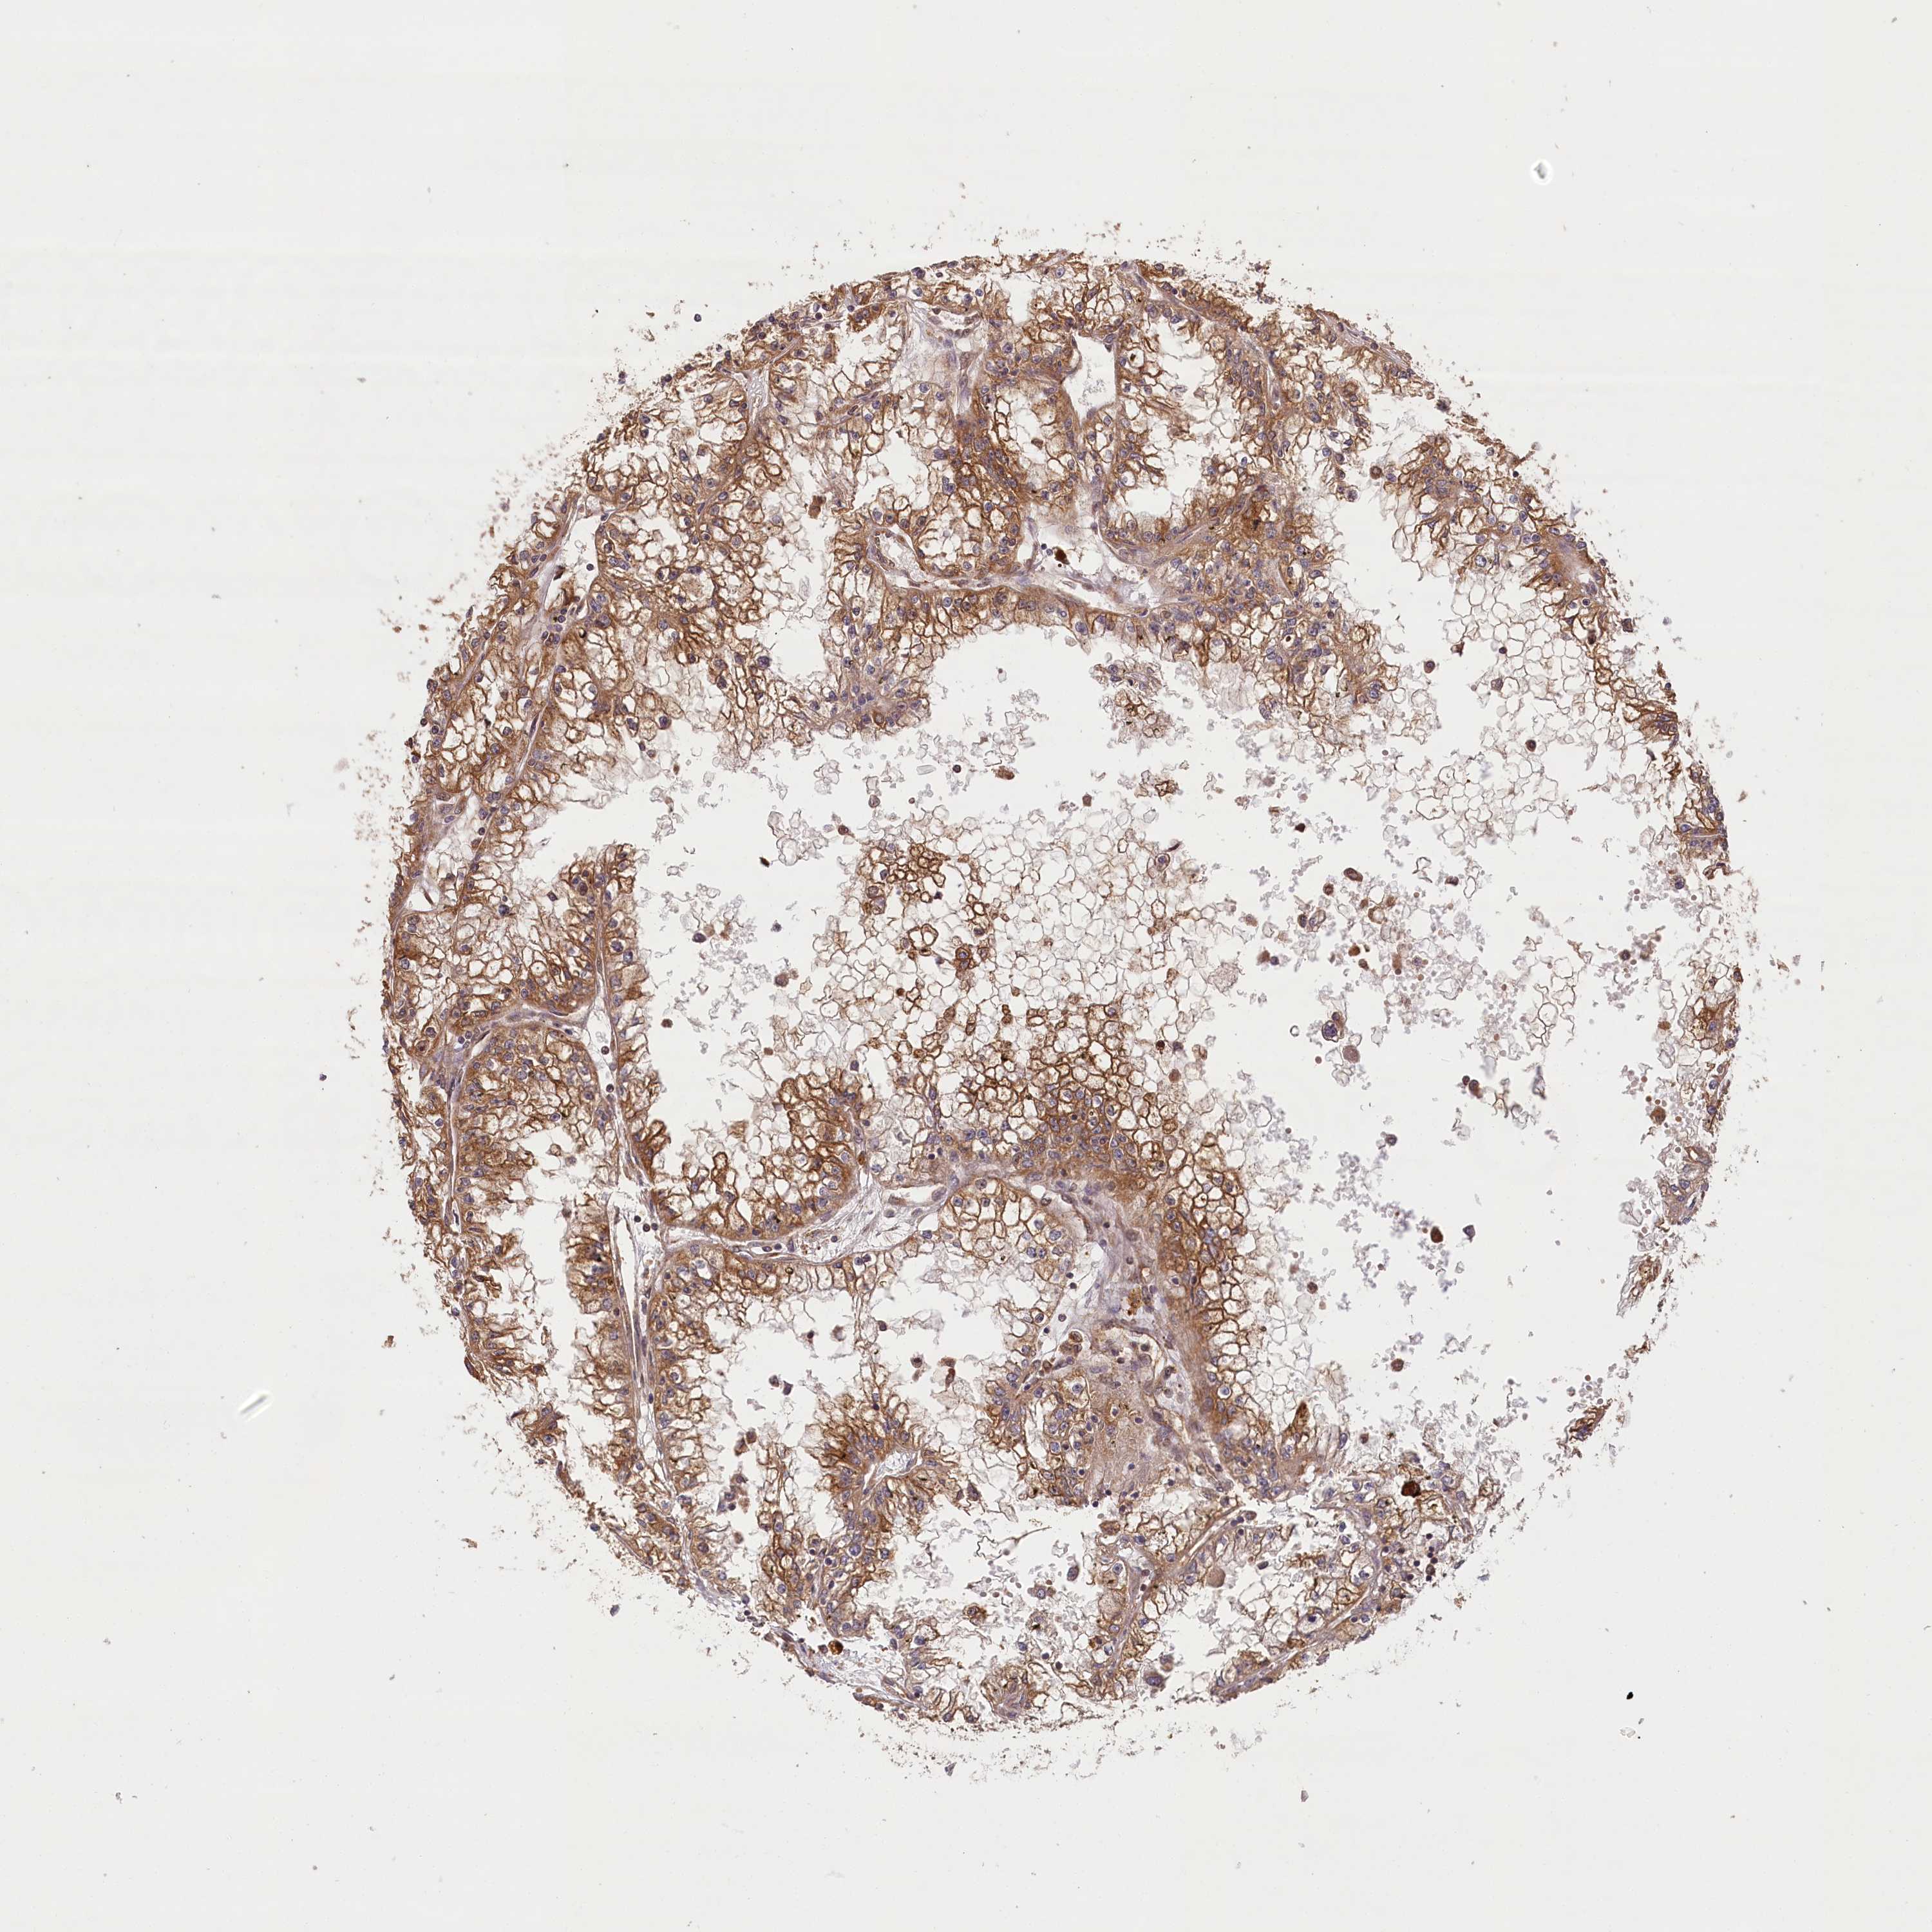

LSS is potential prognostic, high expression is favorable in Kidney Renal Clear Cell Carcinoma (TCGA)

Best expression cut offi

When clicking on this number, the vertical dashed line indicating cut-off, the interactive survival plot, and the Kaplan-Meier curve will be adjusted to show results based on the best expression cut-off.

: 7.32

P scorei

N/A

5-year survival highi

5-year survival lowi

Average pTPM 8.1

Number of samples 521